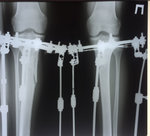

рентген в 60 дней.

Сращение идёт хорошо. Делаем рентген в 90 дней и готовимся к снятию.